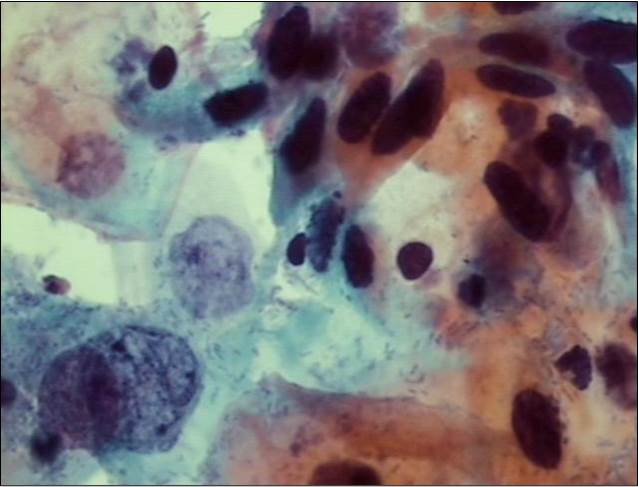

Citología

Estudiamos e investiga las células, a nivel estructural, fisiológico y bioquímico. A partir de esta prueba, se puede detectar la posible existencia de lesiones pre malignas o malignas o incluso infecciones.